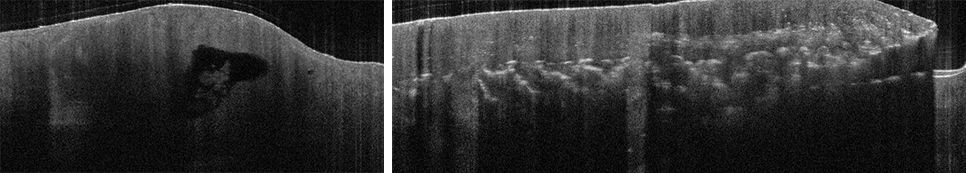

Optische Kohärenztomografie(OCT = Optical Coherence Tomography)

Mit einem OCT-Gerät können ohne Operation ähnlich wie mit einem Ultraschallgerät Schnittbilder der Haut erstellt werden. Durch die Eindringtiefe von ca. 1,5 mm können zahlreiche oberflächliche Strukturen und Prozesse der Haut untersucht werden. Die Untersuchung ist schmerzfrei, ungefährlich sowie schnell und erfolgt innerhalb weniger Minuten.

Dynamisches OCT

Zusätzlich zu den „normalen“ anatomischen Strukturen kann der Blutfluss und damit die Gefäßausstattung eines fraglichen Tumors untersucht werden. Es ermöglicht eine noch genauere Darstellung der Strukturen und eine noch bessere Zuordnung zur definierten Diagnose.